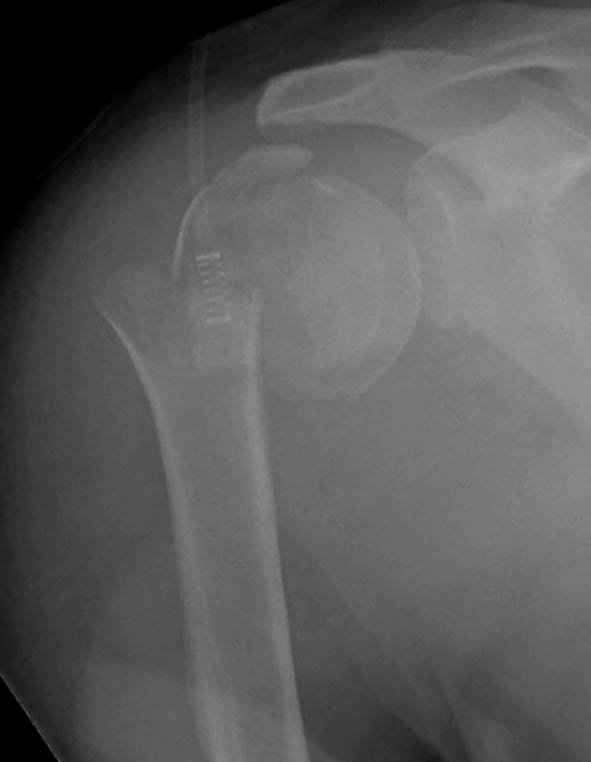

Второй случай, для лечения перелома проксимального

плеча применили пластину "Hand Innovation"

http://www.handinnovations.com/pdf/S3_technique.pdf

Пластина имеет преимущества перед другими "Locking

Implants", потому что пластину можно уложить намного ниже чем другие пластины и имеется возможности проведения шурупов под 130 градусным углом, таким образом можно уменьшить операционный разрез в проксимальной части.

Прооперирован вчера на 13 день после поступления.

Больному 41 и из-за гемодинамической нестабильности в течение первых 7 дней был в реанимации под интубационной седацией.